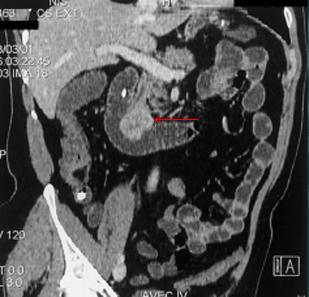

Lipome siegent portion ileo-

coecale . Image TDM en coupe sagitale ( fleche rouge

) |